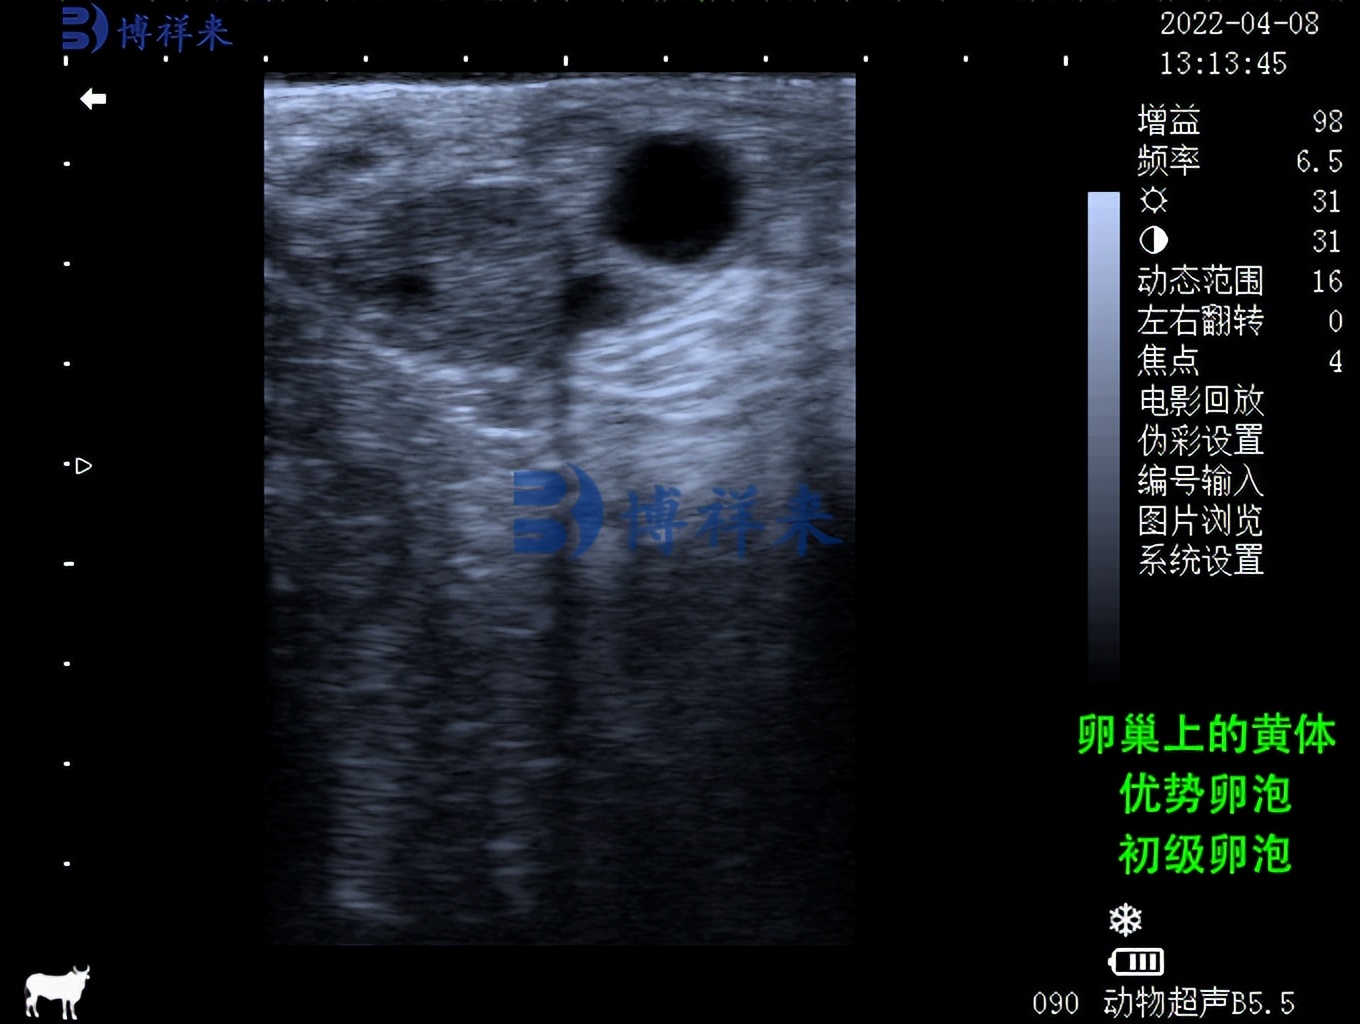

卵巢卵泡的生长和退化长期以来一直是猜测和争论的主题,导致相互矛盾的假设。现在,通过使用超声波,已经确定牛发情周期中的卵泡生长以波浪状模式发生。 尽管有报告表明在每个周期中出现两个、三个,有时甚至四个波,奶牛的两个波模式和小母牛的三个波模式似乎是常态。卵泡波涉及一组卵泡的同步生长,其中一个卵泡获得对其他卵泡的支配地位,成为优势卵泡。每个优势卵泡都有一个生长期和一个静止期,每个持续约5-6天。第一波优势卵泡是无排卵的。它在 4-5 天内保持优势,通常在周期的第 1 或 12 天它失去优势并开始消退。与此同时,第二波卵泡已经募集,第二波优势卵泡的选择已经发生。在双波周期中,这个卵泡继续排卵,而在三波周期中,第二个优势卵泡也退化,为另一群卵泡让路,即第三波。

兽用B超机检测母牛卵巢